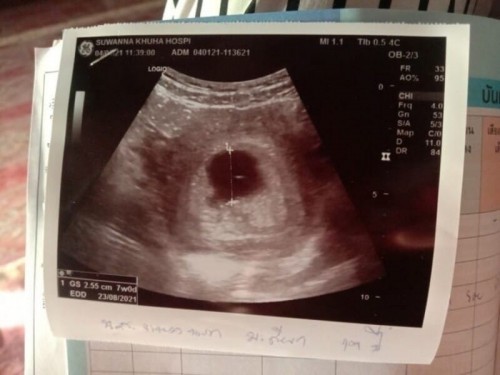

สอบถามแม่ๆหน่อยค่ะ ตอนนี้อายุครรภ์ได้9วีคแล้วแต่อัลตราซาวน์ไม่เจอตัวเด็กเลย แม่ๆมีคำแนะนำไหมค่ะ

น้องตัวเล็กมากๆค่ะอันนี้แม่ซาวน์ผ่านหน้าท้องรึช่องคลอดค่ะ